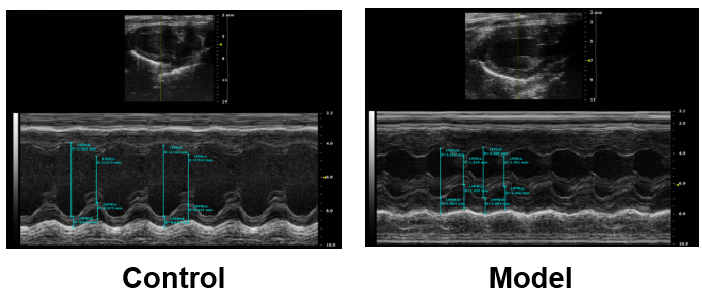

超声检测